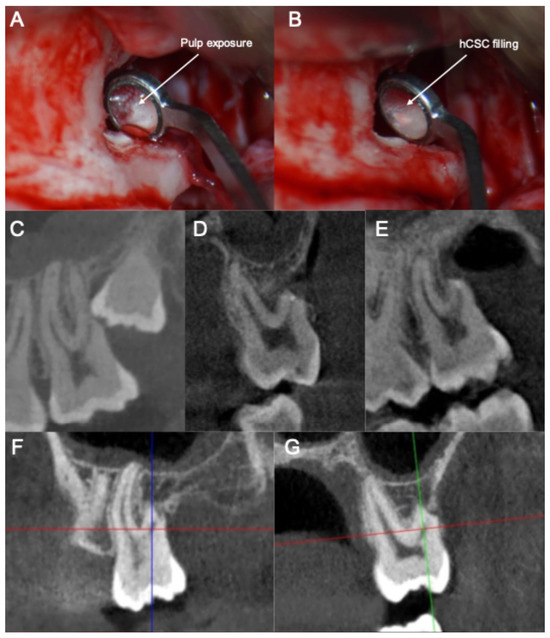

- (1)

- The smoothening of the ERR to allow for a clear visualization and access to the pulp exposure.

- (2)

- The creation of a retrograde cavity and partial pulpotomy of the pulp exposure.

- (3)

- The placement of a pulp capping agent in the cavity over the remaining vital pulp tissue.

| 1-, 3-, 6- and 12-month follow-up | Heat and cold sensitivity tests | Pulp responding normally. Patient is asymptomatic. |

| 24-month follow-up | Heat and cold sensitivity tests; CBCT scan | Pulp responding normally. Patient is asymptomatic. Periadicular endogenous bone apposition observed in the CBCT. |